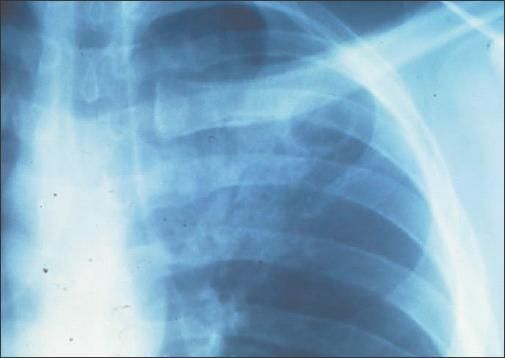

The primary sites of infection are the lung and CNS. Infection can occur at other sites, including the skin, prostate, and eye. Most immunocompromised hosts will present with constitutional symptoms, including fever, malaise, cough, weight loss, or headaches. Chest radiographs may show alveolar or interstitial infiltrates that can be caused by other pathogens1 and thus make diagnosis challenging (Figure 1).

Figure 1 -

This chest radiograph demonstrates pneumonia caused by

Cryptococcus neoformans

infection.